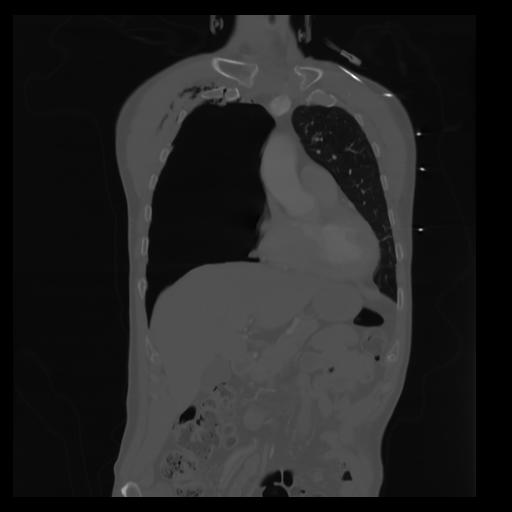

29 CUERPO,CE,Coronal,3.000,CUERPO,Coronal,